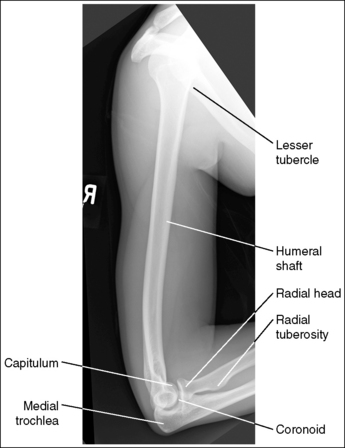

See Figures 4-86 and 4-87 and Box 4-22.

The humerus is in an AP projection. The medial and lateral humeral epicondyles are demonstrated in profile, and the radial head and tuberosity are superimposed over the lateral aspect of the proximal ulna by approximately 0.25 inch (0.6 cm). The greater tubercle is demonstrated in profile laterally, the humeral head is demonstrated medially in profile, and the vertical cortical margin of the lesser tubercle is visible approximately halfway between the greater tubercle and the humeral head.

• An AP projection is obtained by placing the patient in a supine or upright AP projection, with the affected arm extended. Supinate the hand and externally rotate the elbow until an imaginary line drawn between the palpable humeral epicondyles is aligned parallel with the IR (Figure 4-88). This positioning places the proximal radius anterior to the ulna, causing the radial head and tuberosity to be superimposed over the lateral ulna by approximately 0.25 inch (0.6 cm), and places the greater tuberosity in profile.